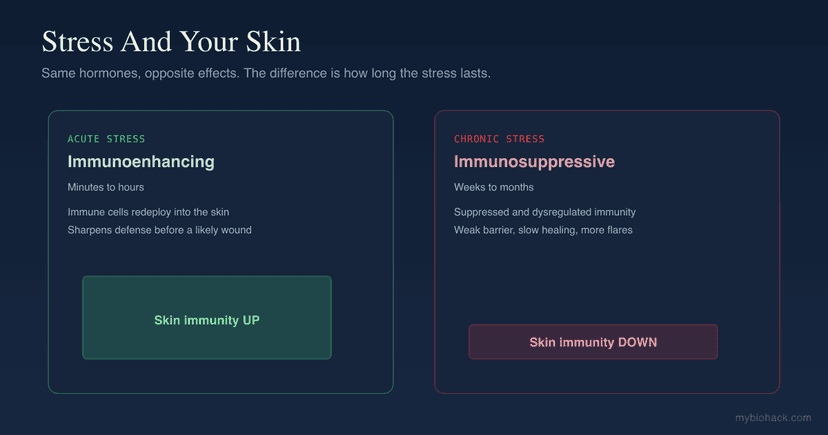

Stress And Your Skin: Why Acute Stress Protects And Chronic Stress Destroys

10 min read